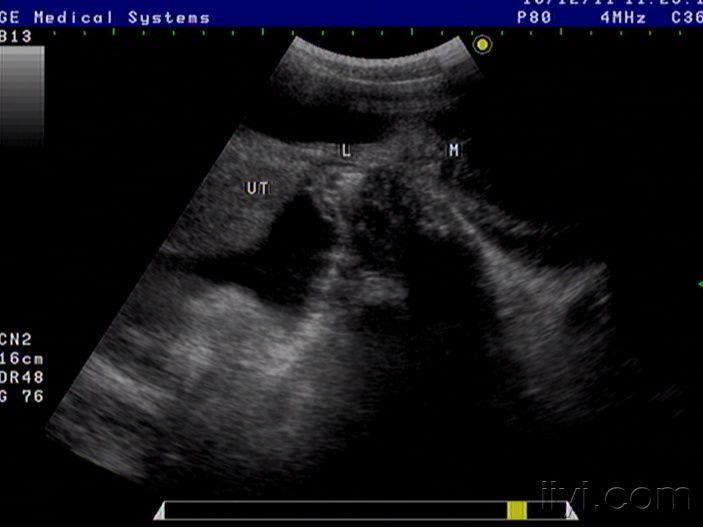

42岁女性患者,自觉腹胀一月余,未诉其它不适,月经规则,彩超中下腹部至盆腔左右各一包块如图,请老师看看像什么,以前没见过这样的这么大的包块

粘液性囊腺癌

是啊,网膜都已经广泛转移了,